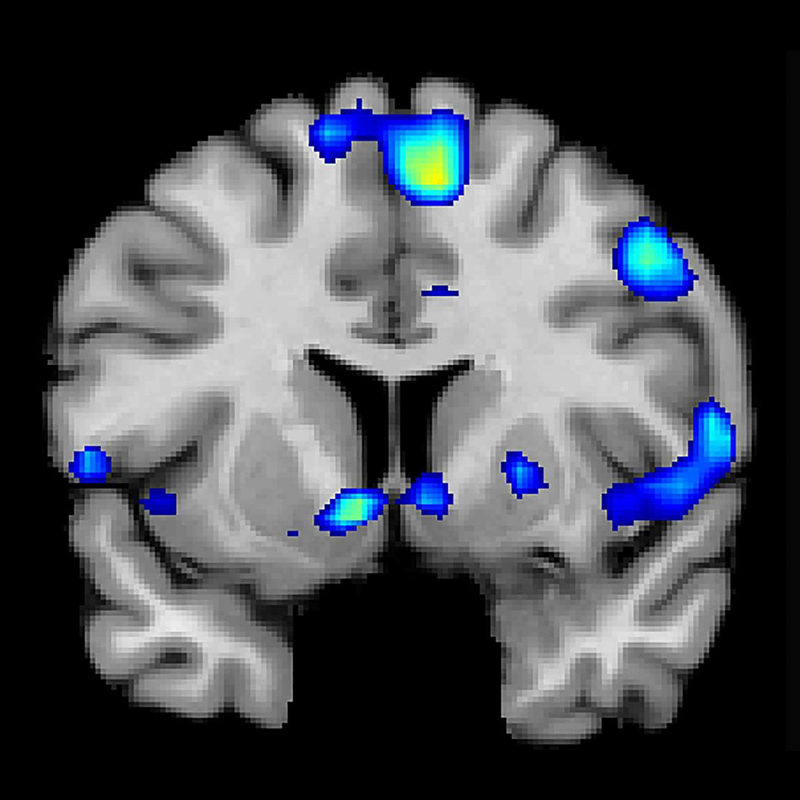

С целью изучить реакцию головного мозга в зависимости от градуса вина Фрост использовал магнито-резонансный томограф и провел специальный анализ мозговой активности с участием 20 добровольцев. По условиям теста, добровольцы должны были продегустировать 8 сортов вина, сгруппированных по две порции. Им нужно было попробовать два вида вин из одного и того же сорта винограда, имеющих аналогичное происхождение, уровень кислотности и содержание сахара. Единственное различие заключалось в уровне алкоголя — в одном он был выше, чем в другом.

После дегустаций исследователи проанализировали реакцию мозга и пришли к выводу, что он активнее реагирует на менее крепкие напитки. Оказалось, что при употреблении вин с низким содержанием алкоголя мозг лучше реагирует на такие параметры, как аромат, запах и вкус вина.